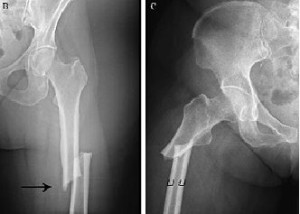

Una revisión sistemática muestra que el tratamiento con bifosfonatos luego de 3 a 5 años puede reducir las fracturas vertebrales, pero no previene las no vertebrales y aumenta el riesgo de complicaciones infrecuentes pero severas. Annals of Internal Medicine, 23 de abril de 2019

Denosumab: efecto rebote y otros efectos indeseados graves

Butlletí Groc vol.31 núm.3 jul-set 2018 El denosumab es un anticuerpo monoclonal que inhibe la resorción ósea producida por los osteoclastos. Fue comercializado en 2010 para el tratamiento de la osteoporosis. En estos años se han identificado varios efectos adversos potencialmente graves: predisposición a infecciones, cáncer, reacciones de hipersensibilidad, trastornos autoinmunes, e incremento de la incidencia de múltiples fracturas vertebrales espontáneas al suspender el tratamiento. En este número revisamos estas novedades.